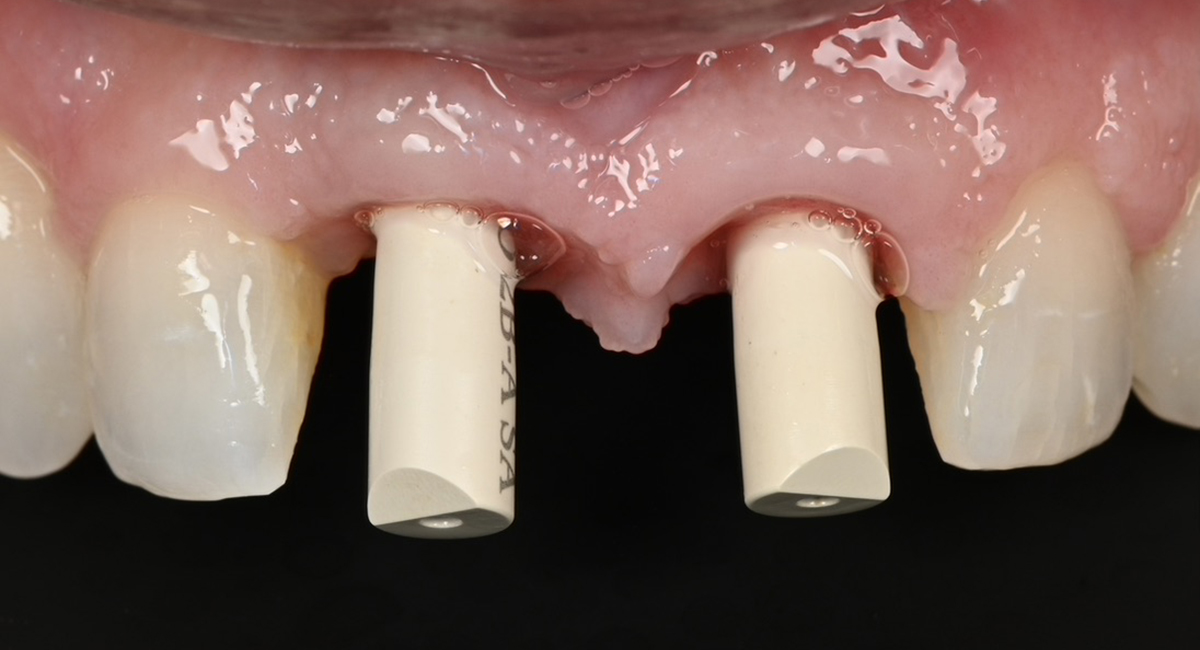

Implant restoration in the esthetic zone often requires well-coordinated interdisciplinary care in order to achieve ideal treatment results. This is especially the case when implants are planned to replace periodontally hopeless teeth. When teeth are extracted, we can typically anticipate 2mm of facial recession. If implants are to be placed following the extraction of hopeless teeth with an already existing gingival height discrepancy, the discrepancy will likely be exacerbated.

The special report presented below illustrates how orthodontic extrusion was successfully used to improve the periodontal architecture prior to the placement of two adjacent implants in the esthetic zone and thus allowed for a more ideal restorative result.